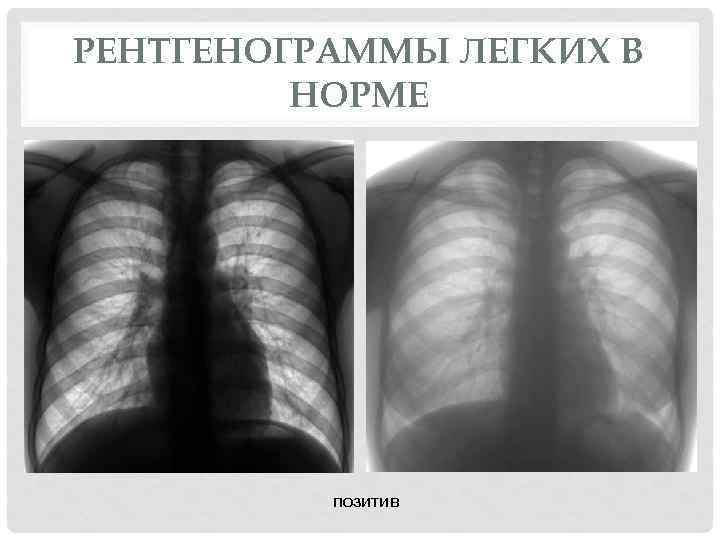

Снимок грудной клетки здорового ребенка: примеры и диагностика